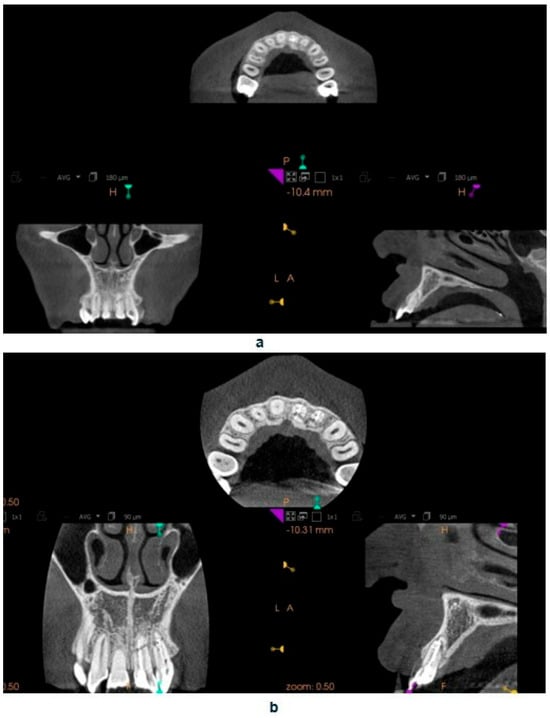

The standard tessellation language (STL) (a file format native to the stereolithography CAD software created by the 3D system) files containing the intraoral scan and the CBCT of the entire dental arch were uploaded into the Blue Sky Plan 4 software. Within this program, a template was designed that included a sleeve intended to guide the endodontic instrument, specifically the Munce Discovery Bur (CJM Engineering, Santa Barbara, CA, USA) used for locating the root canal opening.

Based on the CBCT images and the scans, a template was designed that covers the surfaces of all teeth in the arch, including the palatal and labial surfaces [17]. The template is set to plan the drill position—including the position, length—0 mm, apical diameter—1.05 mm, occlusal diameter—1.55 mm, as well as the dimensions of the software guide tube (offset—10.5 mm—meaning the distance from the tooth, height—5 mm, and guide hole diameter—1.05 mm) (Figure 4a–d). Additionally, the planned length for accessing the root canal will also be determined—18 mm.

Figure 4. Presenting the creation of an endodontic template, (a) settings of drill position in Blue Sky Plan software panoramic view, (b) coronal view, (c) sagittal view, (d) axial view.